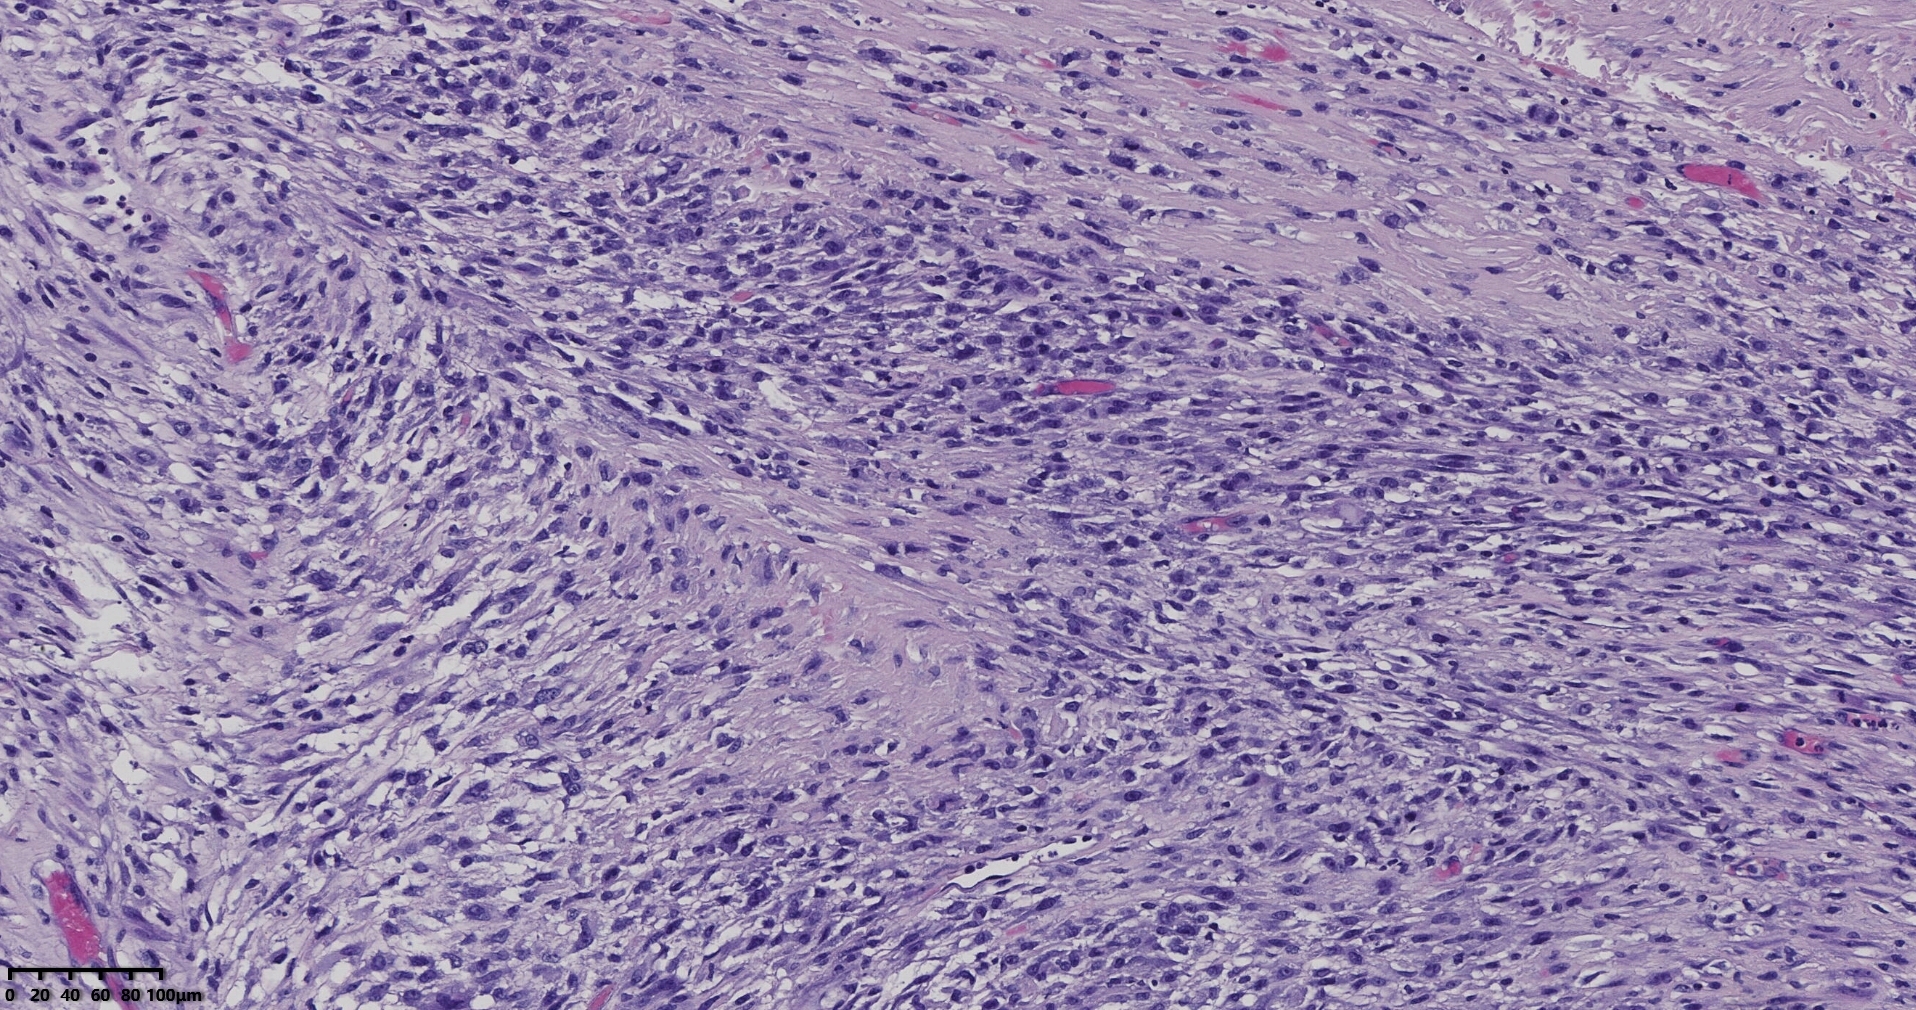

送检灰白肿物十余个,直径多在2-3厘米,切面均为灰白、实性,质地韧,其中一个大肿物,直径约7厘米,切片灰白灰红,质地韧当时取材时印象还是平滑肌瘤,伴变性,不考虑肉瘤,因为形态规整,质地韧,不脆,切面灰白,不是灰黄。

镜下所见小肿物无特殊,大肿物瘤细胞密集,中心区有变性、坏死,瘤细胞核有异型性。大肿物补充取材,发现,部分区域切面灰黄,这个区域,瘤细胞更密集,异型性更显著。肿物边缘有薄层正常平滑肌组织被覆,靠近边缘瘤细胞最密集,局部瘤组织内小血管较丰富。

会诊:考虑平滑肌肉瘤。

北医三院会诊:子宫平滑肌瘤伴红色变性可能性大,建议加做免疫组化及NGS检测进一步明确诊断。